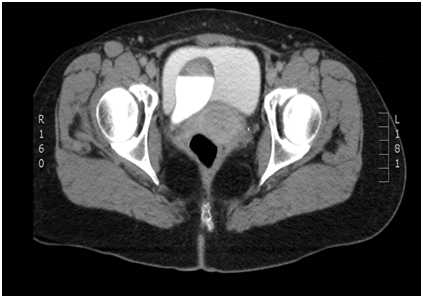

54-year-old female presents to the emergency department with complaint of obstructive voiding, urine leakage, and pelvic pain within troital bulge. She denies any prior irritative voiding symptoms, recurrent urinary tract infections, flank pain or gross hematuria. On physical exam she was found to have a 3x2.5cm mass protruding from her urethra with active urine leakage from her ureteric orifice (Figure 1). Manual reduction was attempted at bedside, but was not pursued because of pain. Previously, the patient was evaluated with CT scan for microscopic hematuria, which showed a ureterocele with associated megaureter (Figure 2). Further evaluation with a voiding cystourethrogram did not reveal reflux and cystoscopy confirmed a single ureterocele without any other bladder masses (Figure 3). During this acute event of urinary retention, the patient stated that shep referred minimally invasive management, and she was taken urgently to the OR for reduction of her ureterocele under anesthesia. Again, manual reduction was attempted, however was unable to be performed. A 22 french rigid cystoscopy was then utilized with constant, even pressure to reduce the ureterocele. After complete reduction, cystoscopy was performed demonstrating bilateral brisk efflux and a 16 french catheter was placed with return of clear yellow urine. She was discharged to home later that day with the catheter in placed. It was subsequently removed a week later and the she was able to void with a post void residual less than 50ml. Follow up nuclear medicine functional study was performed that showed preserved renal function without evidence of obstruction. She has since been asymptomatic since reduction.

Figure 2 CT Urogram excretory phase.